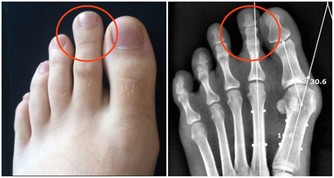

在臨床上,經常能看到患有腎結石的人,但是患者本人往往意識不到,腎結石的常見臨床表現有哪些呢?